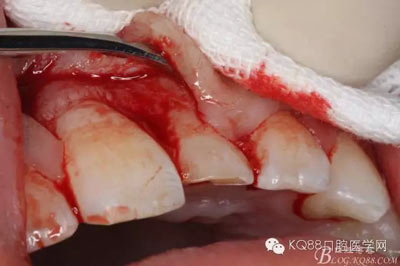

圖5.局部無痛麻醉下。行唇側(cè)齦溝內(nèi)切口

圖6.雙側(cè)垂直附加切口,形成梯形瓣

圖7.翻瓣、注意是全厚瓣。

圖8.翻開牙齦粘膜瓣,可見左乳Ⅰ根方骨面隆起